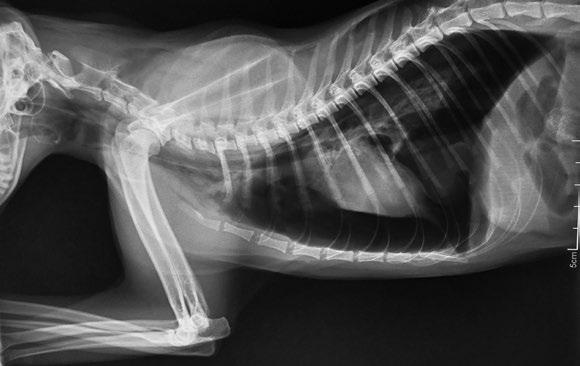

Abdomen

Al contrario que pasa con el tórax, el abdomen debe ser una zona con mayores miliamperajes y mayores kilovoltajes para mayor definición de los órganos. Es necesario incluir el abdomen en su totalidad, desde el diafragma hasta la entrada a la cavidad pélvica. El haz de rayos se debe centrar a nivel de la última costilla para la evaluación de abdomen craneal y a nivel del abdomen medio para la exploración de abdomen caudal.

Asimismo, se debe disparar en fase de espiración para que los órganos abdominales se encuentren lo más separados posibles entre sí y de esta forma evitar superposiciones anatómicas.

Las proyecciones que se piden son la ventrodorsal o lateral ( figura 3 ) en posición laterolateral izquierda. Se deben extender las extremidades anteriores y posteriores en su totalidad. En ocasiones y en especial para ver el tracto gastrointestinal se deben solicitar las dos proyecciones, para poder compararlas.

Figura 3. Proyección lateral de abdomen. Dilatacióntorsión de estómago. Figura 1. Proyección lateral de tórax. Neumotórax. Figura 2. Proyección ventrodorsal de tórax. Metástasis pulmonar.